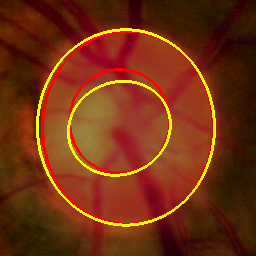

Medical image segmentation is a primary task in many applications, and the accuracy of the segmentation is a necessity. Recently, many deep learning networks derived from U-Net have been extensively used and have achieved notable results. To further improve and refine the performance of U-Net, parallel decoders along with mask prediction decoder have been carried out and have shown significant improvement with additional advantages. In our work, we utilize the advantages of using a combination of contour and distance map as regularizers. In turn, we propose a novel architecture Psi-Net with a single encoder and three parallel decoders, one decoder to learn the mask and other two to learn the auxiliary tasks of contour detection and distance map estimation. The learning of these auxiliary tasks helps in capturing the shape and boundary. We also propose a new joint loss function for the proposed architecture. The loss function consists of a weighted combination of Negative likelihood and Mean Square Error loss. We have used two publicly available datasets: 1) Origa dataset for the task of optic cup and disc segmentation and 2) Endovis segment dataset for the task of polyp segmentation to evaluate our model. We have conducted extensive experiments using our network to show our model gives better results in terms of segmentation, boundary and shape metrics.